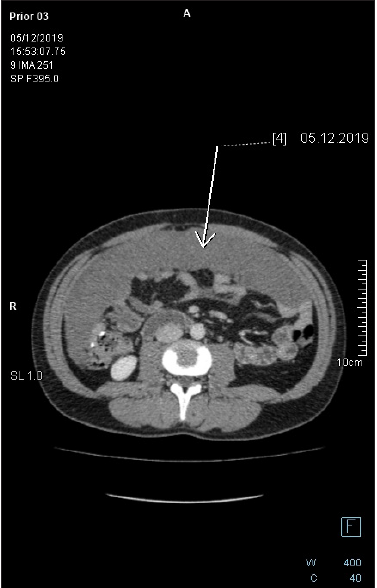

Figure 7: Axial-CECT of the mid-abdomen reveals large pericolonic mucinous lesion. The lesion is homogenous with no soft tissue component, no appreciable septation nor calcification. There is no fat stranding in the adjacent fat tissue.